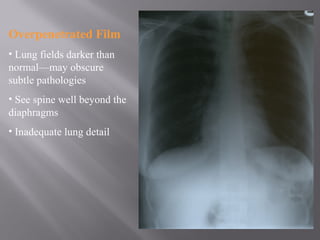

Overpenetrated Film

• Lung fields darker than

normal—may obscure

subtle pathologies

• See spine well beyond the

diaphragms

• Inadequate lung detail

Overpenetrated Film • Lungfields darker than normal—may obscure subtle pathologies • See spine well beyond the diaphragms • Inadequate lung detail